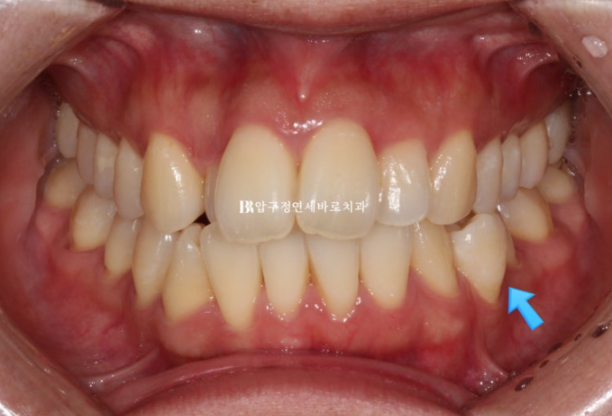

반대쪽 파란 화살표 부분 작은 어금니 역시 배열에서 튀어나가 있어서 윗니와 거꾸로 물리는 반대교합입니다.

치료 시작 후 5개월째의 모습입니다.

24.07

송곳니에 붙은 것은 고무줄 거는 버튼입니다.

위 아래 견치간 폭경 밸런스를 위해 마지막 한 달 간 고무줄을 걸었습니다.

덧니 작은어금니를 제 위치로 넣기 위해 아래는 앞니 포함 9개 치아에 MTA 장치를 붙이고 배열했습니다.